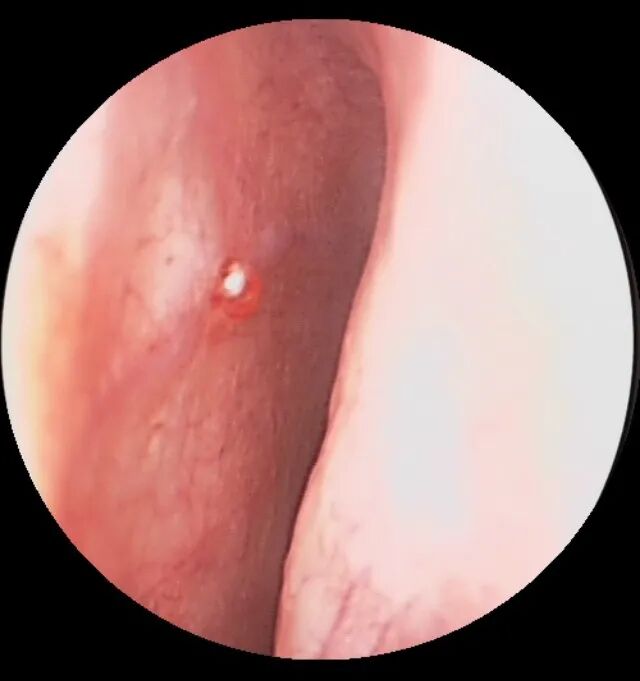

1. 首先,需要在鼻内镜下寻找出血点,这个在门诊进行即可。如下图可以看到鼻腔出血的部位,粘膜表面有小血管喷出血液,这便是明确的出血部位。

图:右鼻黎氏区见小动脉断端喷射出血